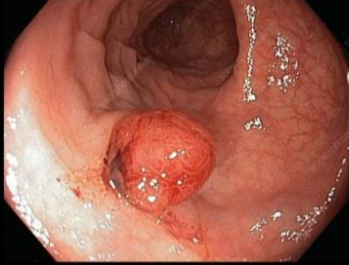

38 year old male smoker present with epigastric pain, endoscope revealed the following picture

Q1- what is your diagnosis? Gastritis

Q2- what is your management?

- Stop smoking,

- Give PPI and analgesic other than NSAID

colonscope view of 58 year male complained rectal bleeding

diagnosis

Colonic polyp

Common type lesion ademp,atpis

1- What is your diagnosis?

Sessile colonic polyp.

2- What is the important significant of it ? It has high potential for malignancy.